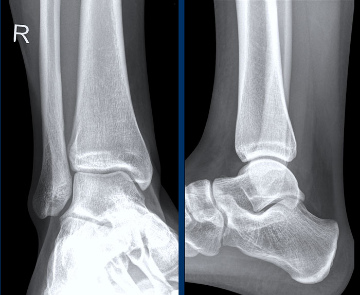

X-ray 1 X-ray 2